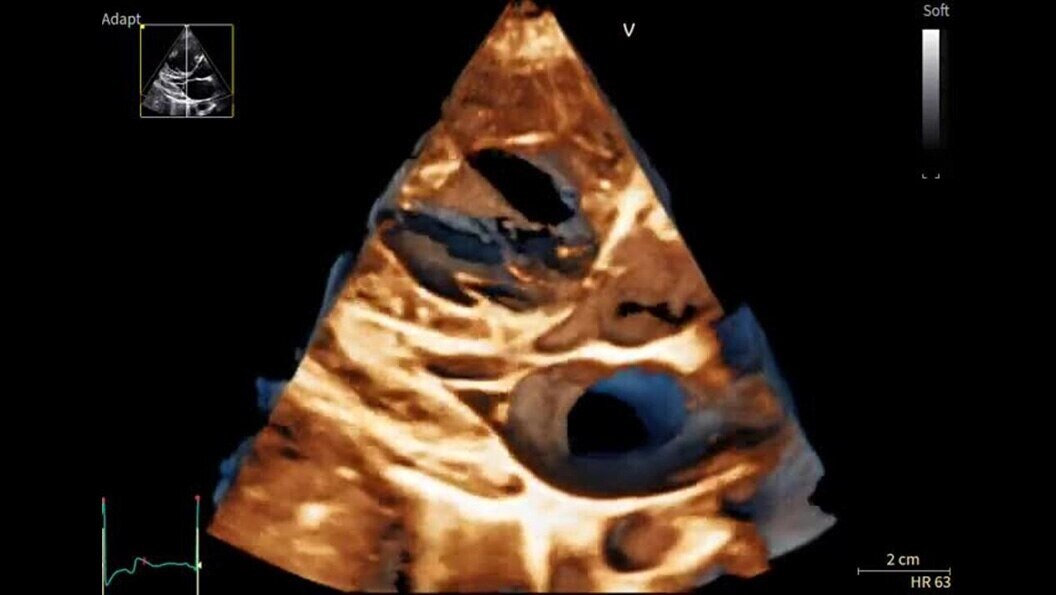

Designed to take you further, next-generation cSound Pioneer works in harmony with our sophisticated probe technology to deliver enhanced detail, a new level of Color Flow, and incredible 4D imaging for clinical confidence from the first scan.